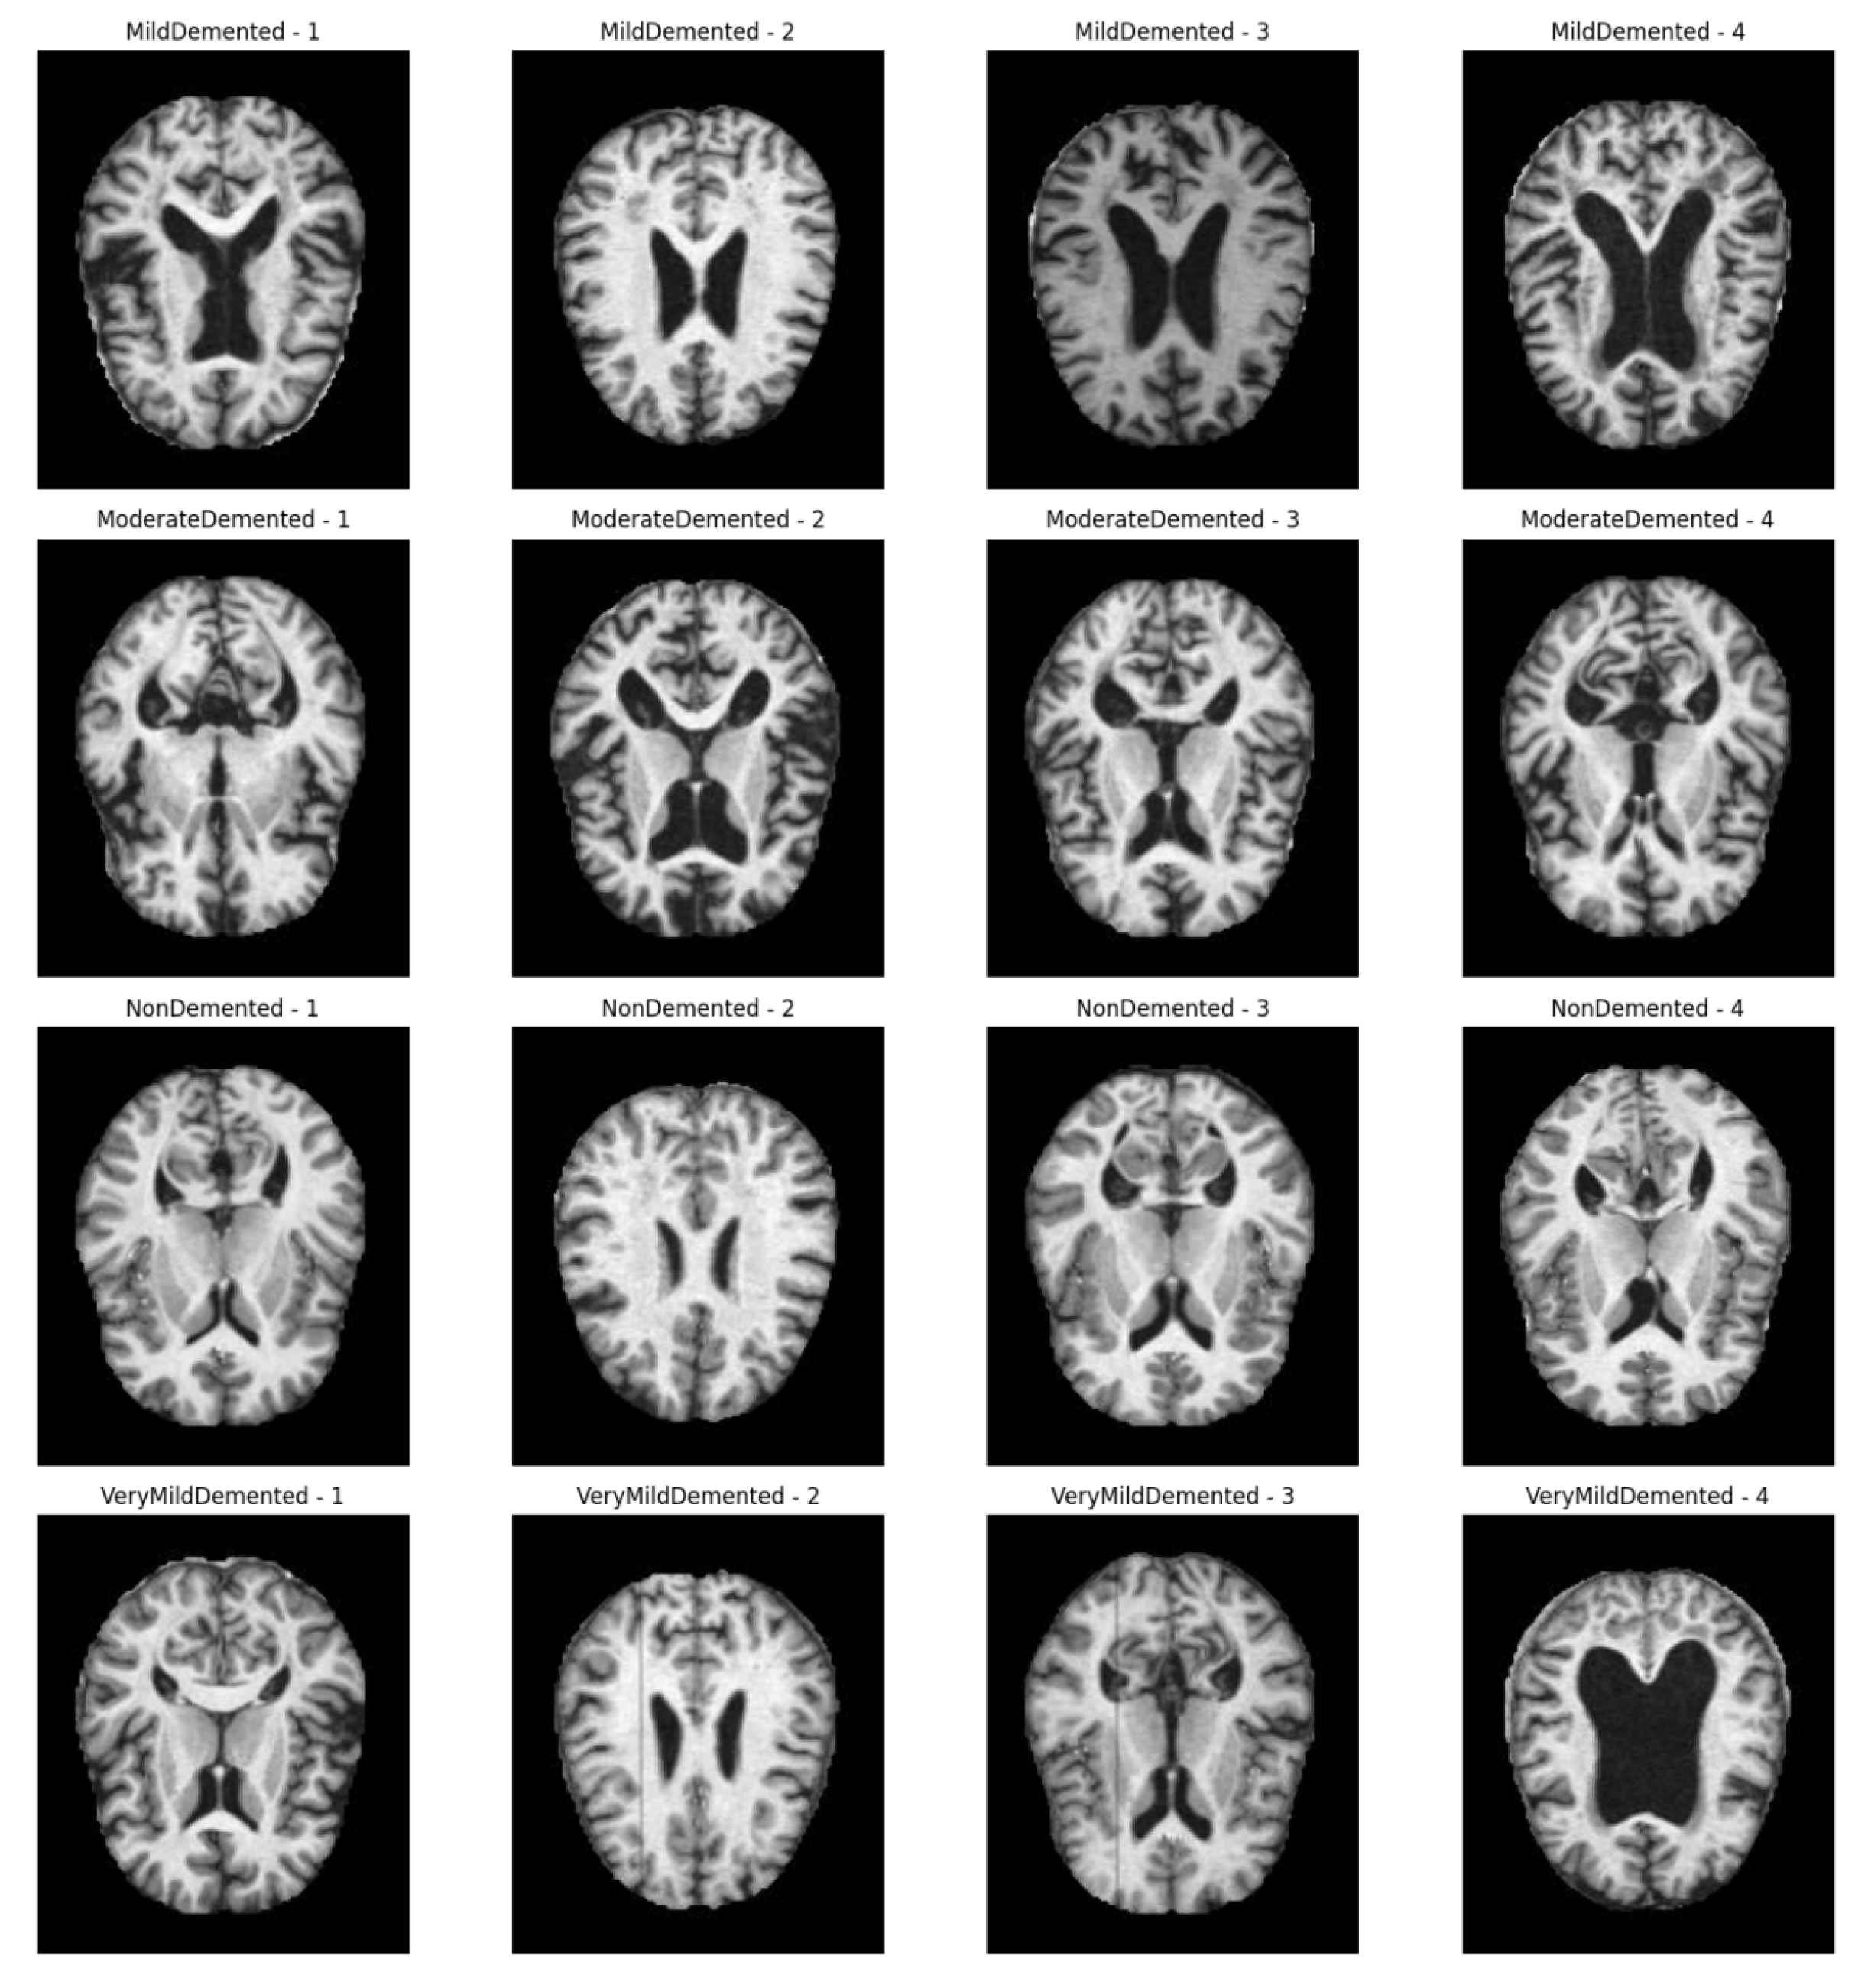

4.1. Data Set

| categories | Number of images after data enhancement |

Number of training sets |

Number of test sets |

|---|---|---|---|

| MildDemented | 8,960 | 7,168 | 1,792 |

| ModerateDemented | 6,464 | 5,171 | 1,293 |

| NonDemented | 9,600 | 7,680 | 1,920 |

| VeryMildDemented | 8,960 | 7,168 | 1,792 |

| total |